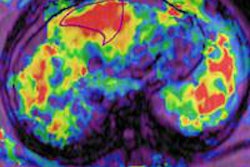

The real-time MRI-guided navigation system is designed for minimally invasive neurosurgery procedures and has been used at the hospital for deep brain stimulation surgery to treat pediatric dystonia while a patient is under general anesthesia.

ClearPoint allows surgeons to see brain tissue without using radiation to obtain images during surgery, MRI Interventions said.